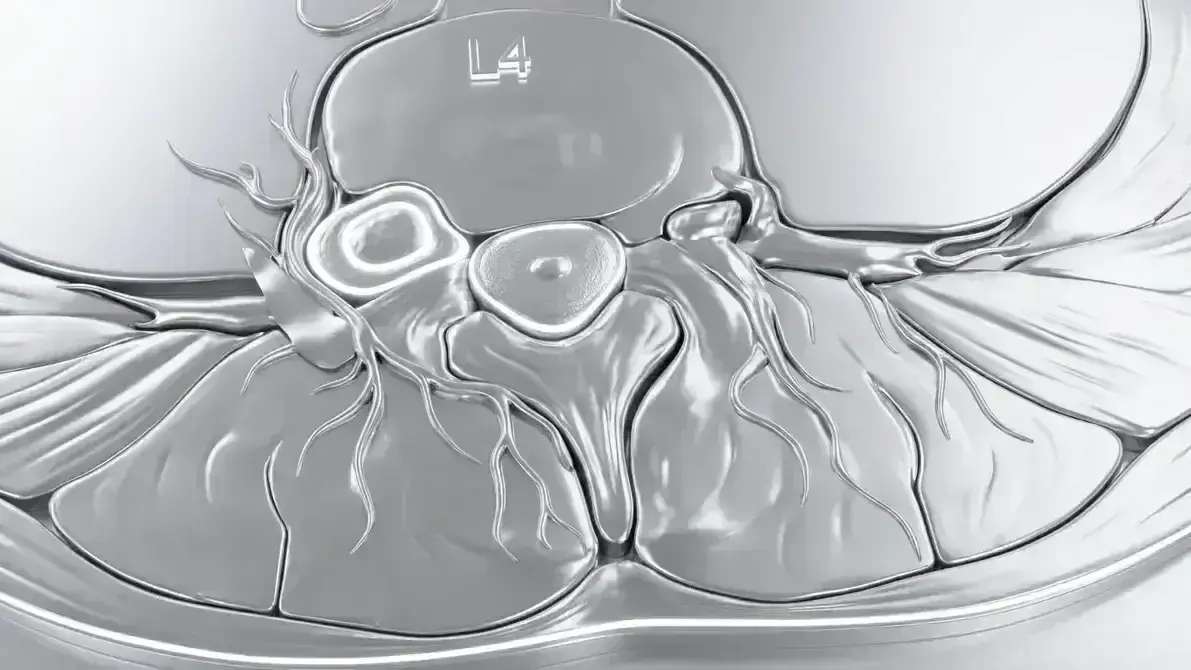

🦴 Schwannoma Espinhal Lombar

Tumor benigno (Grau I) que nasce das células de Schwann das raízes nervosas da coluna lombar. É intradural-extramedular (dentro da dura, fora da medula). Geralmente solitário, bem encapsulado, e não invade a medula — apenas comprime por fora.